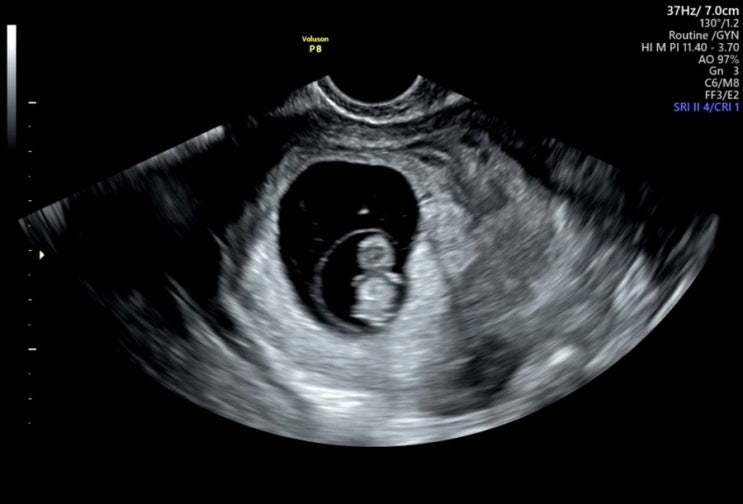

[9week] 분당여성제일병원 분만병원으로 전원하기 졸귀탱 젤리곰 아기 초음파

오늘 드디어 분만병원으로 전원을 하였다 기형아 검사 1,2차를 같은 병원에서 해야하는데 이왕이면 분만병...